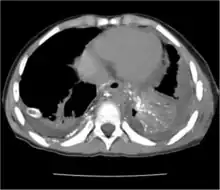

Chest X-rays can detect a chylothorax. It appears as a dense, homogeneous area that obscures the costophrenic and cardiophrenic angles. Ultrasounds can also detect a chylothorax, which appears as an echoic region that is isodense with no septation or loculation. However, neither a normal chest x-ray nor an ultrasound can differentiate a chylothorax from any other type of pleural effusion.[1]